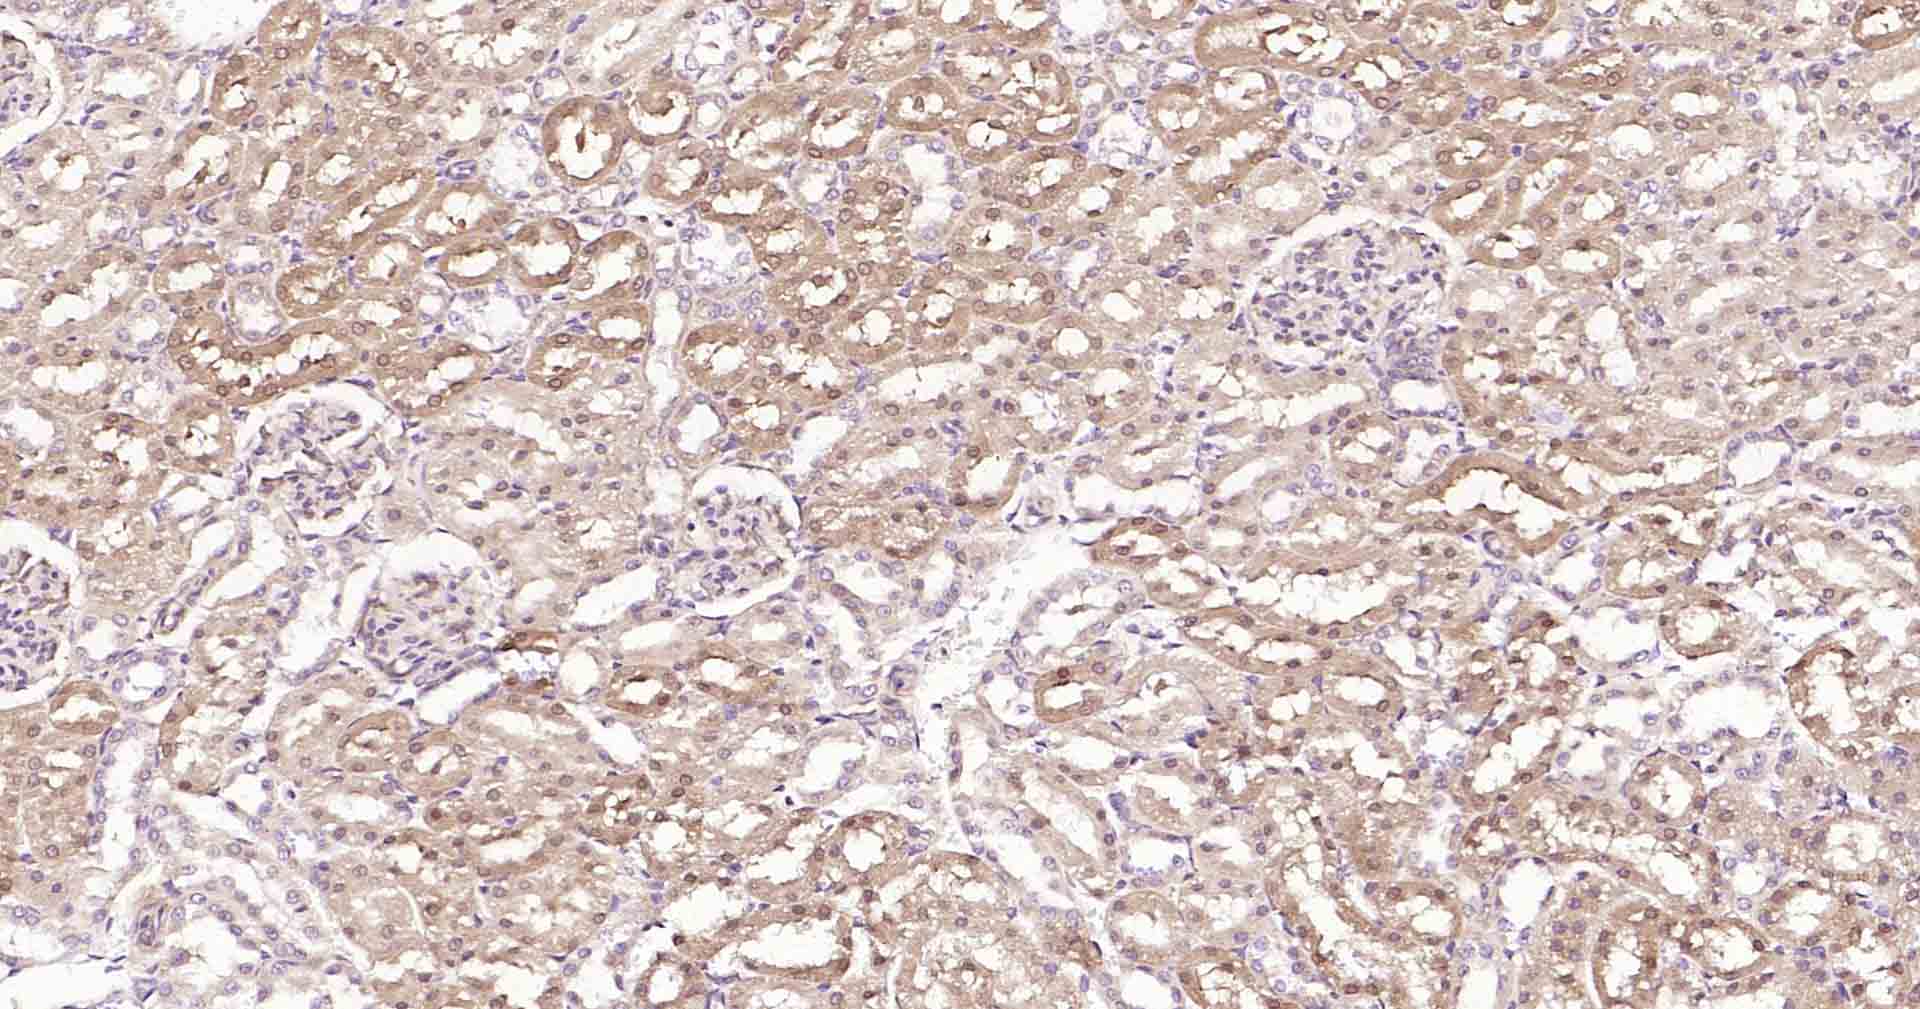

GADD153抗体-bs-20669RGADD153抗体-bs-20669RGADD153抗体-bs-20669RGADD153抗体-bs-20669RGADD153抗体-bs-20669RGADD153抗体-bs-20669RGADD153抗体-bs-20669RGADD153抗体-bs-20669RGADD153抗体-bs-20669RGADD153抗体-bs-20669RGADD153抗体-bs-20669R

IHC-PHuman, Mouse, RatCow1:50-200

IHC-FHuman, Mouse, RatCow1:50-200